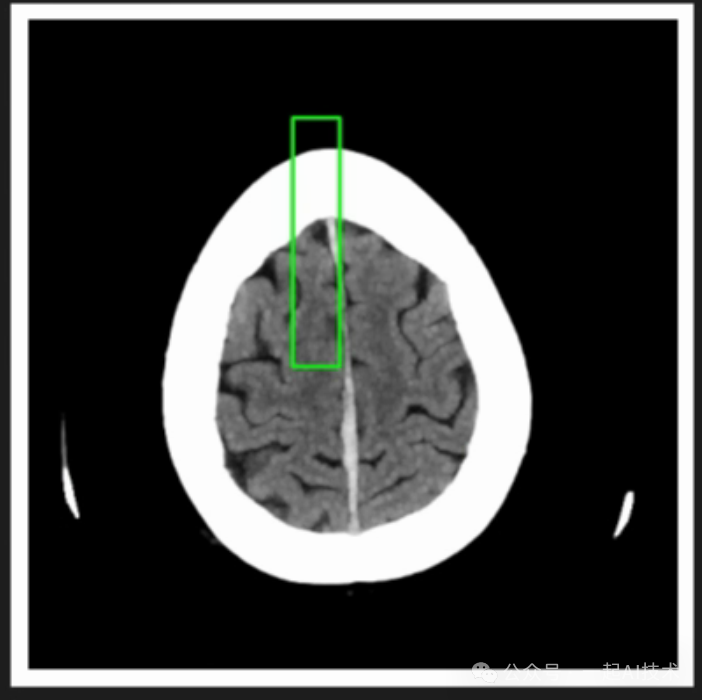

可以看到,经过微调后的模型,可以给出具体区域存在的可能异常问题。

9.2 实际诊断

接下来,我将使用微调后的模型,为家里老爷子的CT片做诊断,看看模型给出的诊断与大夫的异同点。

我总计测试了CT片上的52张局部结果,其中具有代表性的为上述三张,可以看到模型还是比较准确地诊断出:脑部有垂体瘤,可能会影响到眼部。这与大夫给出的诊断和后续检查方案一致。